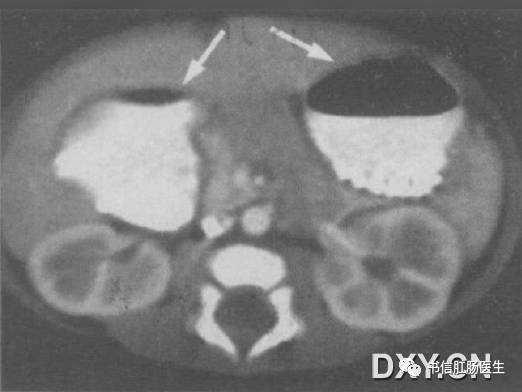

4.双泡征

★ 男婴,14 天,CT 上可见「双泡征」(箭),肠系膜上动、静脉排列正常

■ 影像表现:腹部 X 线平片上表现为上腹部出现 2 个含气囊腔样结构,分别位于左上和中线右侧略偏下,立位可见液气平面,远端无充气或仅有少量充气。该征象还可见于上消化道钡剂或超声检查。

■ 征象解析:双泡征是新生儿或婴儿十二指肠梗阻的特异性表现。十二指肠梗阻时,梗阻近端的十二指肠和胃呈进行性积气、积液并扩张,形成所谓的双泡征。

■ 讨论:双泡征多见于十二指肠闭锁,也可见于十二指肠狭窄、环状胰腺或肠旋转不良等。根据双泡征及其伴随征象可大体判断梗阻的程度及原因,若双泡较大且远端充气,则提示十二指肠完全梗阻(十二指肠闭锁);双泡较小且远端有或多或少的充气,则多为不全梗阻(肠旋转不良、十二指肠狭窄、环状胰腺等)。

另外,当不全性梗阻因气体未进入梗阻远端或梗阻远端少量充气被肠壁吸收,可表现为单纯的双泡征。另一方面,当双泡征远端肠管充气时,并不能排除完全梗阻的可能,因十二指肠闭锁合并胆管发育异常时,梗阻近端气体可通过异常胆管进人梗阻远端。因此,在判断十二指肠梗阻程度时,不能依赖于梗阻远端有无充气。而应全面观察,综合分析,必要时行钡剂或超声检查。